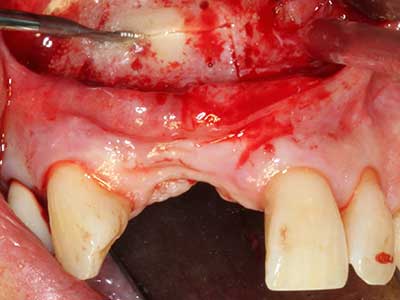

Piezosurgery has additional advantages when harvesting bone blocks. In addition to the high precision with osteotomy described above, the use of the thin saw tips specifically minimizes loss of material. Greater loss of material during harvesting can be expected with the thicker instrument tips, particularly when using Lindemann drills (Lakshmiganthan, Gokulanathan et al. 2012). The basal separation, which is necessary particularly for retromolar block transplants, is simplified by specially designed rectangular saws, with the result that piezosurgery is viewed as a precise, simple and safe procedure for harvesting retromolar bone blocks (Happe 2007) (Fig. 1-12).